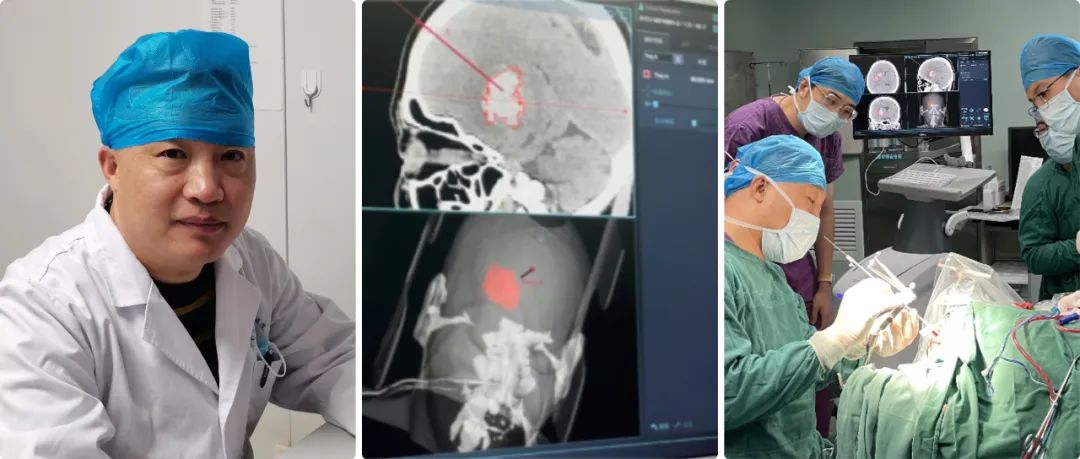

高磊:我院神經(jīng)外科自1998年正式成立,至今經(jīng)過二十余年的努力,已成為濟南市濟陽區(qū)人民醫(yī)院發(fā)展最為迅猛的學(xué)科之一??剖议_放床位45張,其中搶救、監(jiān)護床位5張。年門診量5000余人次,年收治患者2600余人次,每年完成各類手術(shù)400余臺,其中危重的病人手術(shù)170-200例左右。

高磊:濟陽區(qū)人口約53萬左右,我們是濟南市黃河以北地區(qū)重型顱腦外傷、出血性腦血管病及其它腦科急癥救治中心,區(qū)內(nèi)腦出血危重癥基本上都到我們醫(yī)院就診;我們治療范圍也輻射了周邊縣/區(qū),但是量不大。

高磊:隨著現(xiàn)在交通法規(guī)的日益完善,現(xiàn)在顱腦創(chuàng)傷的病人正在逐年的減少,自發(fā)性腦出血的病人卻在逐年的增多,所以科室也從單純的顱腦創(chuàng)傷逐步成為集顯微神經(jīng)外科、立體定向神經(jīng)外科、血管內(nèi)介入神經(jīng)外科等多個亞學(xué)科的綜合性神經(jīng)外科,下一步以腦血管病為主要救治方向。

但是大部分病人雖然是腦出血,但是病人生命體征比較穩(wěn)定,我們盡可能用神經(jīng)導(dǎo)航來實現(xiàn)微創(chuàng)血腫穿刺引流。

神經(jīng)導(dǎo)航微創(chuàng)手術(shù)就避免了傳統(tǒng)開顱手術(shù)的弊端,它可以實現(xiàn)精準(zhǔn)穿刺血腫引流,病人一次性接受手術(shù),恢復(fù)比較快,并對病人整體創(chuàng)傷很小。

高磊:準(zhǔn)備做神經(jīng)導(dǎo)航手術(shù)之前,我們給患者進行顱腦CT薄層掃描,層厚大約在0.625毫米-1毫米,然后在神經(jīng)導(dǎo)航系統(tǒng)進行重建,在重建虛擬像上選擇合適的靶點。

靶點選擇的三個原則:第一,從頭皮到血腫的穿刺路徑比較短;第二,避開大腦重要功能區(qū);第三避開重要的神經(jīng)血管。

我們經(jīng)過對病人注冊,實現(xiàn)在電腦上與實際人頭部位置融合,再根據(jù)電腦上確定的穿刺位置,選擇實際病人顱上的穿刺位置,兩者基本上重合,這樣確保穿刺路徑的精準(zhǔn)性。

高磊:華科精準(zhǔn)這款Sinovation神經(jīng)導(dǎo)航系統(tǒng)功能比較完善/強大的,顱腦CT、核磁共振、血管造影等都能實現(xiàn)圖像的重建。

高磊:任何手術(shù)設(shè)備,尤其導(dǎo)航系統(tǒng),漂移不可避免;Sinovation神經(jīng)導(dǎo)系統(tǒng)的誤差可以控制在0.5毫米左右。

我們對腦組織等漂移怎么克服呢?第一精準(zhǔn)定位,第二實時導(dǎo)航,就是穿刺點確定后,我們通過顱骨鉆孔到達皮層,再進行一次注冊和校正偏差,確保漂移減到最小的程度。

高磊:目前我們的導(dǎo)航系統(tǒng)已經(jīng)應(yīng)用了大約半年時間,使用的效果和大家的反響都不錯;導(dǎo)航系統(tǒng),一旦熟悉之后操作比較簡單。

自從引進導(dǎo)航系統(tǒng),我們科室技術(shù)水平得到了大幅的提升,正如剛才所講沒有導(dǎo)航之前,我們腦出血都是手術(shù)開顱,徒手穿刺誤差比較大,穿刺效果也比較差,有時病人的病程住院時間延長了,而且效果也不好。

現(xiàn)在我們有了導(dǎo)航,穿刺技術(shù)可以說得到了質(zhì)的飛躍;在導(dǎo)航輔助下,基本上可以說穿刺百發(fā)百中,病人術(shù)后恢復(fù)也非??欤δ芨纳埔卜浅o@著,科室技術(shù)水平得到了飛躍式的提升,區(qū)域及周邊病人的社會評價也反響很好。